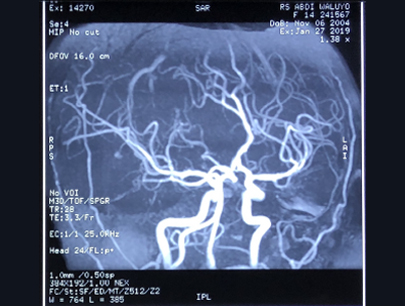

AVM (Arterivenous Malformation)

Kelainan pembuluh darah otak non-stroke

SEBELUM

SESUDAH

(Perempuan, 14 tahun)

Diagnosis: Malformasi Arteri-Vena Oksipital Kanan

Sebelum Gamma Knife

• Nyeri Kepala

3 bulan Setelah Gamma Knife

• Kebutaan menetap

• Penonjolan mata kiri berkurang

Diameter Nidus: 1.5 cm

Nidus tidak ada